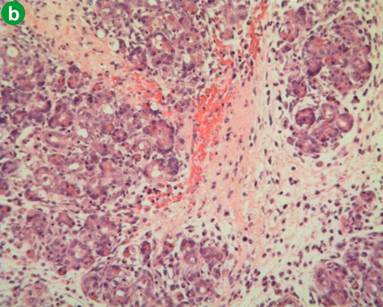

H&E preparations of pancreatic parenchyma in the control group is shown in Figure 4a. Induction of pancreatitis was associated with diffuse injury characterised by oedema, polymorphonuclear leukocyte infiltration and acinar cell disruption. There were also areas of haemorrhage and necrosis (Figure 4b). Xigris® given prior to induction was associated with a significant reduction in the degree of pancreatic injury (Figure 4c). In contrast, Xigris® administered after induction of acute pancreatitis was associated with similar patterns of injury to the acute pancreatitis group (Figure 4d). There was no associated increase in pancreatic parenchymal haemorrhage in either group receiving Xigris®. Histological injury scores were significantly different among groups (P<0.001; Kruskal-Wallis). Post-hoc analysis with Bonferonni adjustment revealed higher scores in the acute pancreatitis group in comparison to both control and the group receiving Xigris® prior to induction of acute pancreatitis (control vs. acute pancreatitis: P=0.001; acute pancreatitis vs. Xigris® pre-acute pancreatitis: P=0.004; Mann-Whitney) (Figure 5). Scores in the acute pancreatitis group differ significantly from the Xigris® post-acute pancreatitis group (P=0.039; Mann-Whitney). With reference to haemorrhage there was no significant difference among groups (P=0.196; Kruskal-Wallis) (Figure 6).

Figure 4. H&E preparations of pancreatic parenchyma in the four groups. a. Representative control animal (original magnification x10). b. Representative L-arginine-induced acute pancreatitis animal. Note extensive disruption of acinar architecture with necrosis and haemorrhage (original magnification x10). c. Animal pre-treated with Xigris®. Note in particular the preservation of acinar cell architecture and the absence of haemorrhage (original magnification x40). d. Animal treated with Xigris® after the induction of pancreatitis. Note extensive disruption of acinar architecture, oedema and inflammatory cell infiltrate (original magnification x10). |